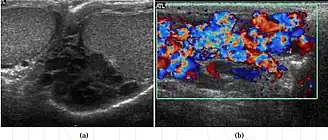

O diagnóstico do varicocele pode ser feito pelo exame físico e anatômico, usando manobras que aumentem a pressão abdominal (como tossir, força de defecação) para fazer as veias incharem enquanto o médico ou enfermeiro palpa o plexo pampiniforme. Para confirmar o diagnóstico deve ser feito um exame chamado Eco Doppler, no qual é possível verificar se realmente há refluxo de sangue, além de conseguir medir a intensidade desse refluxo. Os vasos do plexo pampiniforme apresentarão dilatação superior a 2 mm.[2]

- ↑ Bucci, Stefano; Liguori, Giovanni; Amodeo, Antonio; Salamè, Leonardo; Trombetta, Carlo; Belgrano, Emanuele (2007). "Intratesticular varicocele: Evaluation using grey scale and color Doppler ultrasound". World Journal of Urology 26 (1): 87–9. doi:10.1007/s00345-007-0216-1. PMID 17962950.